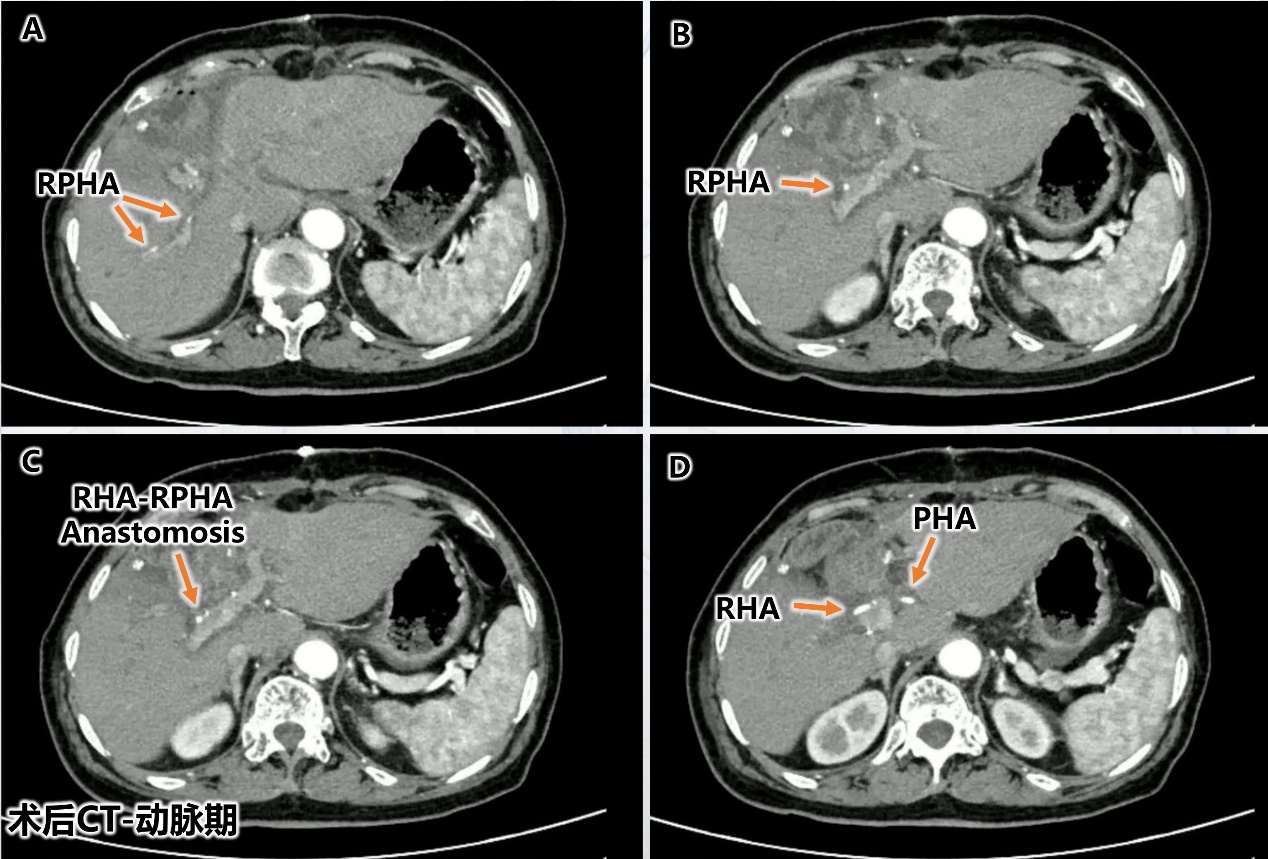

手术中最关键、最富挑战性的环节在于肝动脉的切除与重建。术中,主刀医生需要将直径不足 3 毫米的右肝动脉主干与直径更是不足 2 毫米的肝右后动脉进行端端吻合。这要求手术团队具备高超的显微外科技术和稳定的心理素质。最终,团队凭借在血管精细解剖与吻合方面积累的深厚功底,成功完成了毫米级的动脉吻合重建。术中超声实时监测确认血流畅通无阻(对应图 4),术后增强 CT 也再次证实了重建动脉的通畅,肝脏血供良好,未见缺血表现(对应图 5)。